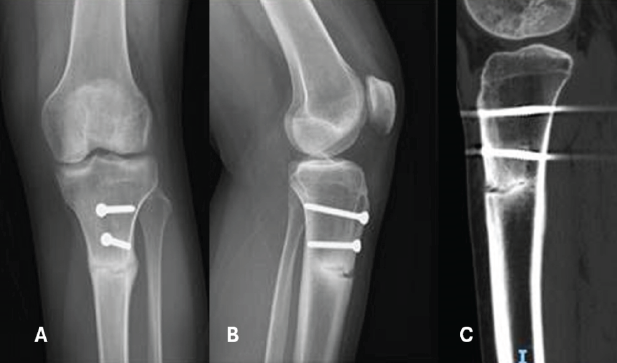

Throughout the 6 weeks, the knee’s range of motion was progressively restored, with flexion not exceeding 90°. Isotonic knee-locking exercises were postponed for 6 weeks, while isometric contractions were encouraged. During a 3-month follow-up outpatient visit, X-rays confirmed the spontaneous onset of a stress fracture of the proximal tibia below the TTO site, showing signs of progression on the next follow-up (Fig. 2). The patient was advised to limit sports activities and postpone dancing. However, the 10-month follow-up evaluation revealed a significant progression of the fracture line, involving two-thirds of the entire tibial diameter, leaving just the posterior cortex intact (Fig. 3).

Figure 3: Anteroposterior view (a), lateral view (b), and sagittal computed tomography image (c) demonstrate the critical progression of the fracture line, involving two-thirds of the entire tibial diameter.